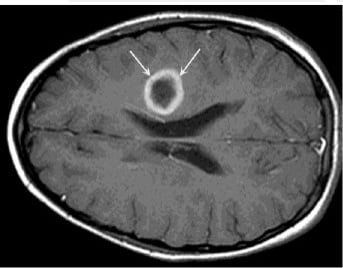

Так как симптомы, которыми характеризуется абсцесс мозга, не имеют определенной специфики и схожи с таковыми при других мозговых поражениях, важна дифференциальная диагностика абсцесса головного мозга. Обычно она заключается в проведении томографии с контрастом — МРТ или КТ.

- На ранних стадиях оптимальной является МРТ, так как КТ может «не заметить» воспаление ткани. На этапе инкапсуляции компьютерная томография становится информативной. Как правило, периферия очага на снимке принимает круглые очертания, так как контрастное вещество накапливается по контуру капсулы. На ранних этапах на МРТ-изображениях оценивается интенсивность сигнала энцефалитического очага.